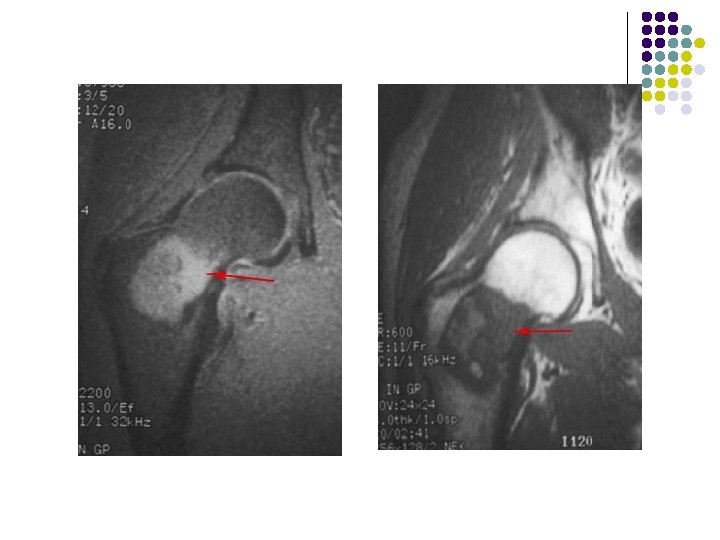

Axial ct of proximal leg-Soft tissue attenuation with well defined margins and foci of low attenuation within due to h’age or necrosis. Coronal CT scan of a giant cell tumor of the distal ulna show soft tissue attenating lesion.

T 2 -weighted coronal MRIs of the wrist show a giant cell tumor located in a subarticular position in the distal radius. The lesion is heterogeneous and hyperintense.